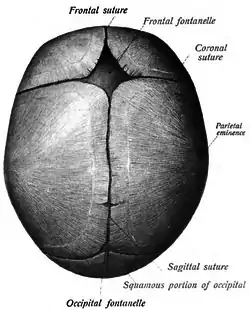

![]() Human adult skull from above. Sagittal suture labeled at center. | |

The sagittal suture, also known as the interparietal suture and the sutura interparietalis, is a dense, fibrous connective tissue joint between the two parietal bones of the skull. The term is derived from the Latin word sagitta, meaning arrow.

The sagittal suture is formed from the fibrous connective tissue joint between the two parietal bones of the skull.[1] It has a varied and irregular shape which arises during development.[1] The pattern is different between the inside and the outside.[1]

Two anatomical landmarks are found on the sagittal suture: the bregma, and the vertex of the skull. The bregma is formed by the intersection of the sagittal and coronal sutures. The vertex is the highest point on the skull and is often near the midpoint of the sagittal suture.